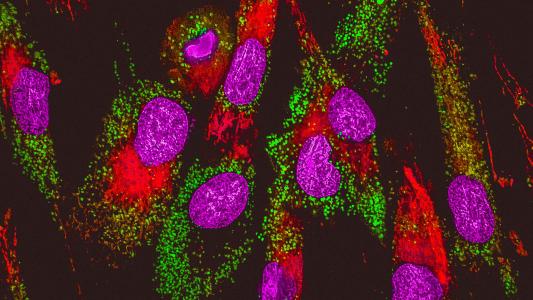

Study may explain why cancer gets more aggressive as we age

A molecule in the blood of older people promotes the spread of cancer, which could explain the link between age and metastatic cancer.